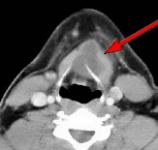

Fig.1 Fig.2 Fig.3 Fig.4

CLINICAL PRESENTATION: This patient presented with a mid-line and left paramidline mobile neck mass and was referred to AIC for a helical CT scan of the neck soft tissues.

HELICAL CT FINDINGS: The CT scan was performed on AIC’s Multi-slice, Multi-detector Helical CT Scanner with 2.7 mm axial sections at 2.5 mm intervals before and during infusion of low-osmolar, non-ionic contrast using a power injector. It shows a lobulated cystic mass (arrows) in the neck at and below the hyoid bone in the midline and to the left of it, with portions of it behind the hyoid bone and portions embedded in the left strap muscle.